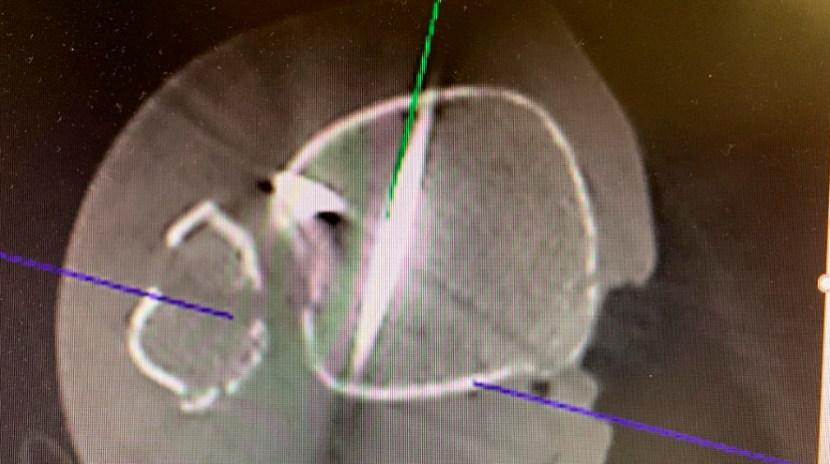

经一长约1厘米的纵向皮肤切口,显露胫骨前侧皮质。在透视引导下,并使用两把小号Longbeck拉钩保护伸肌腱及神经血管结构,将一枚用于4.5毫米无头双螺纹加压螺钉的1.6毫米导针,从前内侧向后外侧、以约5-10°的向远端倾斜角置入(图3b–d)。经术中三维透视确认导针位置正确后(图3e),测量所需螺钉长度。

(e)

图3. (a–e): (a) 使用尖头复位钳临时固定;(b) 从前向后置入1.6毫米导针;(c) 踝穴位片,红线标记腓骨切迹后缘,蓝线标记前缘;(d) 点状末端视图证实轨迹位于切迹外;(e) 术中三维透视显示导针正确走行。